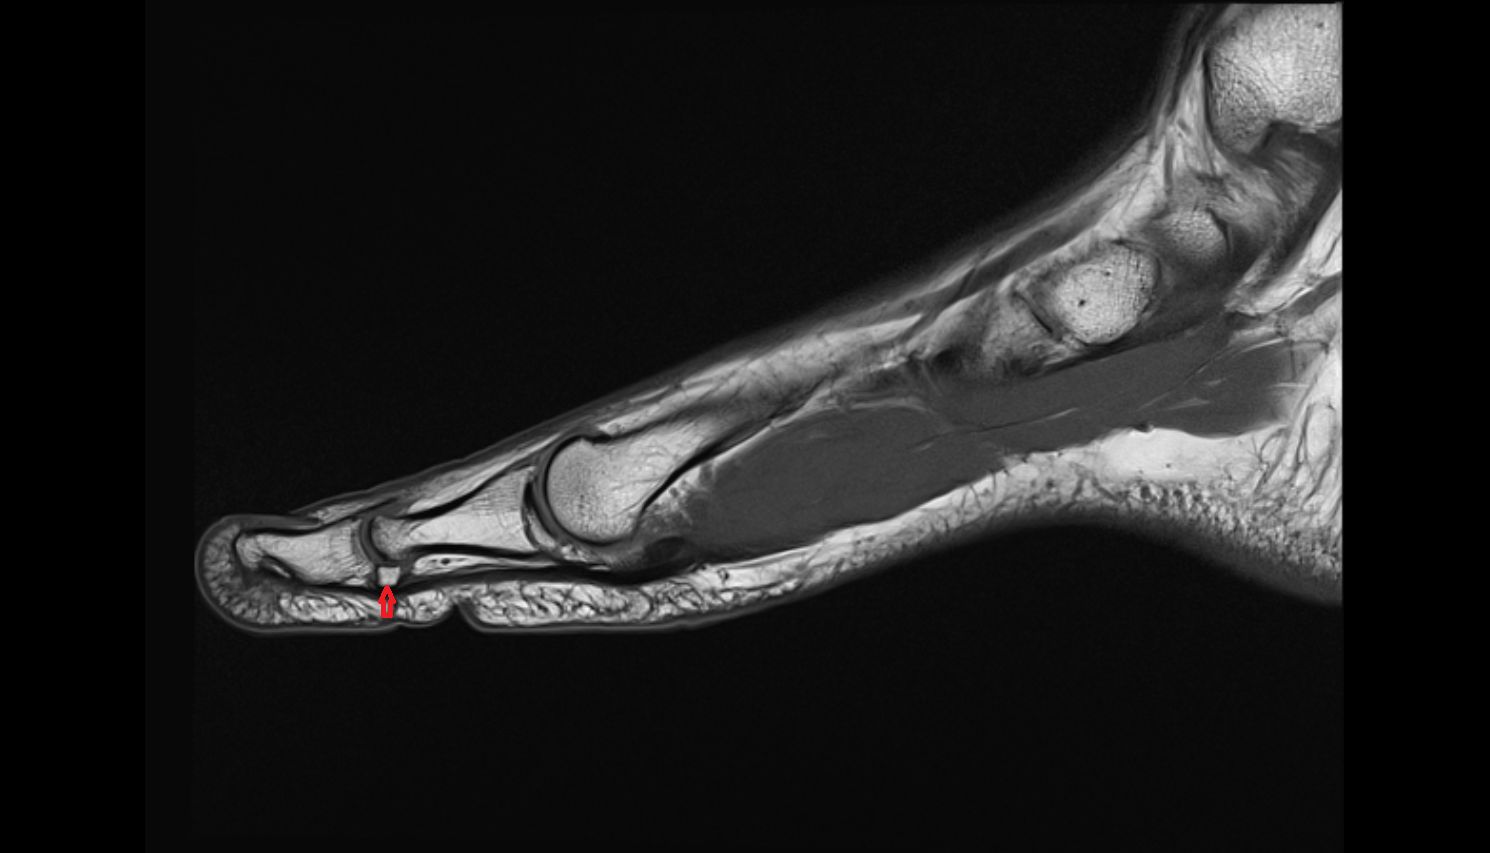

- Proximal phalanx of great toe

- Distal phalanx of great toe

- Sesamoid bone of great toe

- Lateral sesamoid bone

- Medial sesamoid bone

- Plantar plate ligament